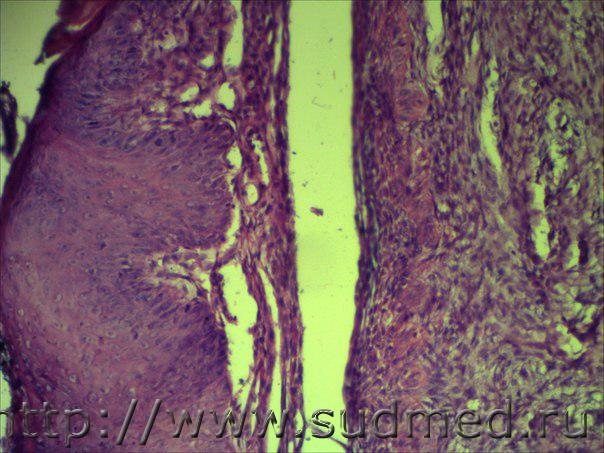

Н/О в ротовой полости в области десны

По многослойным плосколеточным эпителиям слизистой имеет место базальноклеточная нарушение полярности( умеренные признаки дисплазии), а по подслизистой строме признаки если это действительно макроопухоль, то микроскопически веретеноклеточный(фиброзный) эпулис!

Похоже на эпулис.

Аналогично.